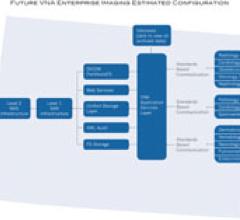

Centura Health is the largest healthcare network in Colorado. Dedicated to delivering advanced care to more than a half million people, Centura strives for the highest quality and continuous innovation. To accomplish this, the organization needed to address its transformation and connectivity efforts across patient, people, processes and technologies — the essential ingredients when optimizing clinical performance. Centura understands that by mastering clinical image data across its care network it will enable clinical improvements, optimize electronic medical record (EMR) investments and drive the organization’s interoperability strategy. Centura had several key requirements necessary to adequately consider a VNA solution.